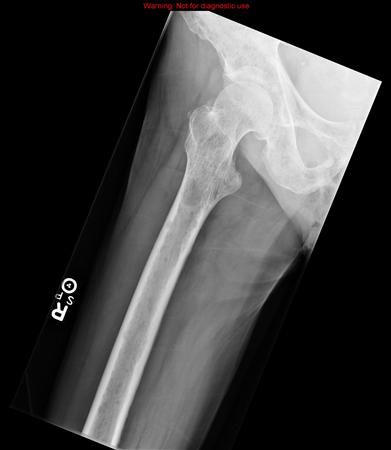

Summary Metastatic Disease of the Extremity is a malignant pathologic process that is the most common cause of destructive bone lesions in the extremities of adult patients. Workup including history, physical, radiographs, and CT chest, abdomen, pelvis identifies the primary tumor in about 85% of cases. In patients where a primary carcinoma is not identified, obtaining a biopsy is necessary to rule out a primary bone lesion. Treatment is aimed at controlling pain, maintaining patient independence, and preventing fractures. Epidemiology Incidence bone is the third most common site for metastatic disease (behind lung and liver) solitary bone lesions are 500 times more likely to be metastatic carcinoma than a primary bone tumor in patients > 40 years old Demographics Age >50 years old Anatomic location most common sites of bony metastatic lesions include spine > pelvis > proximal femur > humerus pathologic fractures secondary to metastatic disease most commonly occur in the proximal femur, followed by the proximal humerus 65% nonunion rate 50% in femoral neck, 20% pertrochanteric, 30% subtrochanteric acral (distal extremities) lesions are rare, but when present are most commonly from lung carcinoma lung primary is the most common for occult metastatic disease Risk factors carcinomas that commonly spread to bone include breast (most common in females) lung thyroid kidney prostate (most common in males) mnemonic: BLT and a Kosher Pickle or PT Barnum Likes Kids Etiology Pathophysiology mechanism of metastasis tumor cell intravasation E cadherin cell adhesion molecule (CAM) on tumor cells modulates release from primary tumor focus into bloodstream PDGF promotes tumor migration avoidance of immune surveillance target tissue localization chemokine ligand 12 (CXCL12) in the stromal cells bone marrow acts as homing chemokine to certain tumor cells and promotes targeting of bone attaches to target organ endothelial layer via integrin cell adhesion molecule (expressed on tumor cells) extravasation into the target tissue uses matrix metalloproteinases (MMPs) to invade basement membrane and ECM induction of angiogenesis via vascular endothelial growth factor (VEGF) expression genomic instability decreased apoptosis thrombospondin inhibits tumor growth lytic lesions osteolytic bone lesions create a "vicious circle" tumor cells secrete PTHrP which stimulates the release of RANKL from osteoblasts RANKL then binds to the RANK receptor on osteoclast precursor cells differentiation to active osteoclasts occurs, which causes bony destruction TGF-B, ILGF-1, and calcium are released from resorbed bone, which stimulates tumor cells to release more PTHrP the tumor continues to grow through the release of growth factors, proinflammatory cytokines (IL-6 and IL-8), and VEGF osteoblastic lesions prostate and breast cancer mets due to tumor-secreted endothelin-1(ET-1) binds to endothelin A receptor (ETAR) on osteoblasts and stimulates osteoblasts ET-1 decreases WNT suppressor DKK-1 activates WNT pathway, increasing osteoblast activity Associated conditions metastatic hypercalcemia a medical emergency symptoms include confusion muscle weakness polyuria & polydipsia nausea/vomiting dehydration treatment hydration (volume expansion) loop diuretics bisphosphonates Anatomy Vascular spread Batson's vertebral plexus valveless venous plexus of the spine that provides a route of metastasis from the lung, kidney, breast, prostate, or thyroid to axial structure including vertebral bodies, pelvis, skull, and proximal limb girdles arterial tree metastasis mechanism by which lung and renal cancer spread to the distal extremities Presentation History may describe night pain weight loss pain with weight-bearing enlarging mass Symptoms pain may be mechanical pain due to bone destruction or tumorigenic pain which often occurs at night typically dull pain with gradual onset pathologic fracture occurs at presentation in 8-30% of patients with metastatic disease 90% of pathologic fractures require surgery rarely have potential to heal metastatic hypercalcemia confusion muscle weakness polyuria & polydipsia nausea/vomiting dehydration Physical exam neurologic deficits caused by compression of the spinal cord in metastatic disease to the spine Imaging Radiographs recommended views plain radiographs in two planes of affected limb including the joint above and below the lesion AP chest findings destructive lesions may be lytic, mixed, or blastic (sclerotic) lung, thyroid, and renal are primarily lytic 60% of breast CA are blastic 90% of prostate CA are blastic cortical metastases are common in lung cancer lesions distal to elbow and knee are usually from lung or renal primary low sensitivity (about 50%) best at assessing lytic lesions may not be able to detect lesions until they are 1-2cm with 50% reduction in bone mineral density CT indications CT of chest/abdomen/pelvis should be obtained to evaluate for a primary tumor in all patients >40-years-old with a lytic bone lesion of unknown origin CT of the lesion may also be obtained to evaluate containment within cortical boundaries sensitivity of 71-100% may be difficult to visualize lytic lesions until there is cortical destruction MRI indications high sensitivity (95%) and specificity (90%). can detect bone marrow changes before osteoblastic lesions develop findings low intensity on T1 high intensity for 2 sensitivity of 82-100% Technetium bone scan indications may be used to identify other skeletal lesions findings myeloma and thyroid carcinoma are often cold on bone scan because it evaluates osteoblastic activity evaluate with a skeletal survey using bone scan and CT identifies the primary tumor about 50% of the time PET scan alone only has 30% specificity Studies Labs CBC with differential ESR BMP LFTs PT, PTT electrolyte panel Ca, Phos, alkaline phosphatase Paget's disease serum and urine immunoelectrophoresis (SPEP, UPEP) multiple myeloma PSA prostate CA LDH lymphoma urinalysis renal CA Invasive studies Biopsy in patients where a primary carcinoma is not identified, obtaining a biopsy is necessary to rule out a primary bone lesion should not treat a bone lesion without tissue diagnosis of the lesion metastatic adenocarcinoma not identified by CT of the chest, abdomen, and pelvis is most likely from a small lung primary tumor Histology characteristic findings epithelial cells in clumps or glands in a fibrous stroma immunostaining Keratin CK7 (breast and lung cancer) TTF1 (lung cancer) Receptor status can provide therapeutic targets during concomitant medical management estrogen, progesterone, and HER2/neu receptor status is essential for treating metastatic breast cancer Differential Differential of Metastatic Disease of Extremity Malignant lesion in older patient Multiple lesions in older patient Epithelial glands on histology Benefits from Bisphosphonate therapy Treatment is wide resection and radiation Metastatic bone disease o o o o o Myeloma o o o Lymphoma o o Chondrosarcoma o MFH / fibrosarcoma o Secondary sarcoma o Pagets disease o o Fibrous dysplasia o Synovial sarcoma o Hyperparathyroidism o Glomus tumor o Soft tissue sarcomas o Non-tumor conditions to consider: osteomyelitis, myositis ossificans, metabolic bone disease, osteonecrosis, synovial proliferative disease Mirels Criteria Mirels Criteria Score Site Size (relative to shaft diameter) Radiographic appearance Pain 1 Upper extremity < 1/3 Blastic Mild 2 Lower extremity 1/3 to 2/3 Mixed Moderate 3 Peritrochanteric > 2/3 Lytic Functional (pain with weight-bearing) Recommendation < 8: radiotherapy and observation 8: use clinical judgment > 8: prophylactic fixation scores of 9 had a 33% risk of fracture Sensitivity 80-90% and specificity 30-35% Treatment Nonoperative indications asymptomatic lesions nondisplaced fractures (in the humeral shaft, pelvis, scapula) non-weight-bearing bones short life expectancy tumors sensitive to systemic therapy bisphosphonate therapy indications used in lytic, blastic, and mixed lesions outcomes reduces rates of skeletally-related events decreased lysis and associated hypercalcemia Denosumab indications bone metastases from solid tumors and multiple myleoma outcomes superior to zoledronic acid in preventing skeletally-related events radiation therapy indications palliation of pain and local tumor control outcomes reduces pain in 70% of patients at 2 weeks with complete pain relief in about 30% renal cell carcinoma is less radiosensitive chemotherapy, immunotherapy, and hormone therapy see table of treatments based on cancer type Operative stabilization of complete fracture, postoperative radiation indications almost always required due to high risk of nonunion fixation should not rely on bone healing (ie using an endoprosthesis for a proximal femur fracture if the patient has a relatively good prognosis) life expectancy > 6 months is the best predictor of fracture healing failure of nonsurgical treatment and pain postoperative radiation all patients require postop radiation unless death is imminent or area has previously been irradiated begin radiation therapy 2-3 weeks after surgery area of irradiation should include the entire fixation device (e.g. entire femur after intramedullary nailing of femoral lesion) prophylactic stabilization of impending fracture, postoperative radiation indications more than 50% destruction of the diaphyseal cortices permeative destruction of the subtrochanteric femoral region >50-75% destruction of the metaphysis persistent pain after radiation therapy pain with weight-bearing outcomes prophylactic fixation leads to greater likelihood of independent ambulation, discharge to home, and shorter hospital stays compared to fixation of completed fracture Wide resection of the bony metastasis provides lower risk local recurrence when compared to intralesional curettage preoperative embolization indications renal cell carcinoma or thyroid carcinoma before operative intervention because these cancers are very vascular palliative pain control in renal or thyroid cancer other minimally invasive techniques radiofrequency ablation: thermal ablation of periosteal nerves cementoplasty: cementing a lytic lesion to improve stability cryoablation: freezes a lytic lesion high-intensity focused ultrasonography: new and less available Techniques Bisphosphonate therapy technique both oral (clodronate) and IV (pamidronate, zoledronic acid) formulas available complications osteonecrosis of the jaw Denosumab technique convenient subcutaneous dosing complications osteonecrosis of the jaw Radiation therapy technique external-beam radiation therapy given as multiple fractions or as a single fraction in high-dose dosage and fraction are determined by location, symptoms, and tumor volume complications risk of fracture (typically 1 year after treatment) Chemotherapy and hormone therapy technique dependent on primary lesion and receptor positivity Stabilization of complete and/or impending fractures, postoperative radiation technique dependent on location proximal humerus arthroplasty or open reduction internal fixation humeral diaphysis intramedullary nail femoral neck arthroplasty/endoprosthetic replacement total hip arthroplasty should be performed if there are acetabular lesions hemiarthroplasty is adequate if no acetabular involvement peritrochanteric cephalomedullary device with +/- cement femoral diaphysis statically locked cephalomedullary nail polymethylmethacrylate can be used to fill defects outcomes humerus length of resected segment related to functional outcome femur arthroplasty has significantly lower failure rates compared to IMN and ORIF higher dislocation rate with THA compared to hemiarthroplasty higher rates of infection seen with arthroplasty compared to nails Embolization technique preoperative embolization performed for renal and thyroid cancers reduces intraoperative blood loss without adverse effects on healing Prognosis Median survival in patients with metastatic bone disease thyroid: 48 months prostate: 40 months breast: 24 months kidney: variable depending on medical condition but may be as short as 6 months or as long as 4-5 years lung: 6-7 months